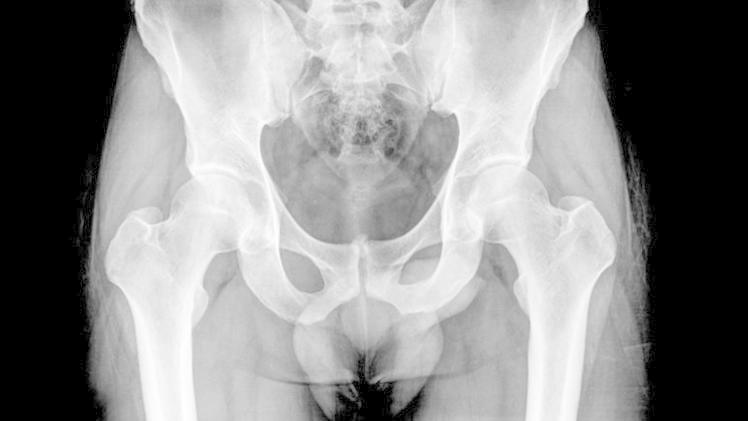

أجرى الأطباء لامرأة تبلغ من العمر 92 عاماً في سان أنطونيو بشيلي، فحصاً روتينياً بالأشعة السينية داخل إحدى المستشفيات، وفوجئوا بوجود شيء غير عادي على الإطلاق داخل بطنها.

فقد وجد الأطباء بقايا جنين مُكلّسة يعتقد العلماء أن المرأة حملتها خارج رحمها لمدة لا تقل عن 50 عاماً، وهذه الحالة الغريبة، "الجنين المكلس"، تحدث عندما يموت الجنين خارج الرحم.

ووفقاً لـمدير المستشفى في تشيلي، كان الجنين المتكلس "كبيراً ومتطوراً"، وربما توفي عندما كان عمره يبلغ 7 أشهر، وكما هو الحال مع معظم حالات الجنين المكلس، كانت المرأة غير مدركة تماماً للجنين الموجود داخل جسمها، والذي احتل معظم تجويف البطن.